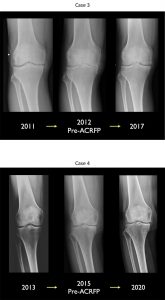

图3动脉再生辅助程序后软骨再生的辐射证据(ACRFP)。

Lyu及其同事在另一项研究中跟踪膝部OA三年后ACFP测试记录他们的膝部评分和膝部受伤和骨髓炎评分团队随后对这些分数进行了预处理和后处理比较结果表明91%的病人对治疗感到满意,即使是那些患有高级(四级)疾病的病人也是如此。确定KSS和KOOS分数后处理提高,显示症状解析和提高生活质量放射结果分析显示80%的病人回转软机变换(图3),而MRI结果研究显示72%的病人回转软机变换(图4)。